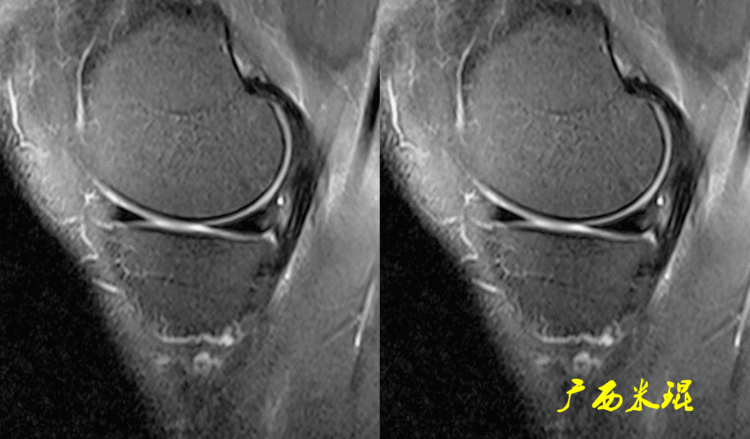

(2)隐窝隐窝是半月板后角与关节囊之间的正常凹陷,与体位等有关,可有可无,一般情况下积液越多隐窝越大,有上下之分,下面这张MR矢状位片见到的是上隐窝,紧贴半月板、光滑、不连通是其特点,也是鉴别要点。

下面这张MR矢状位片见到的是下隐窝,也紧贴半月板、光滑、不连通。